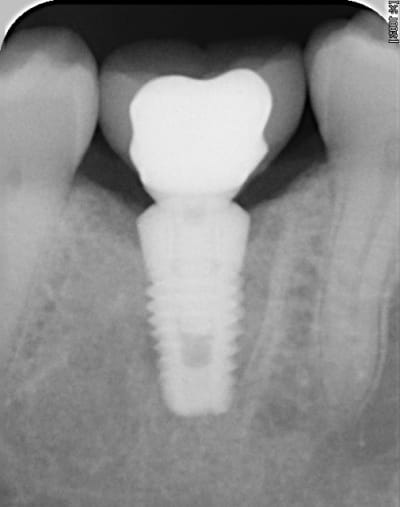

ci-joint ce que donne la connectique sur une rétroalvéolaire

@+

Pas mal la molaire.

Ça fait combien de temps que la couronne est en fonction ?

sur la radio, la couronne est en place depuis 8 mois.